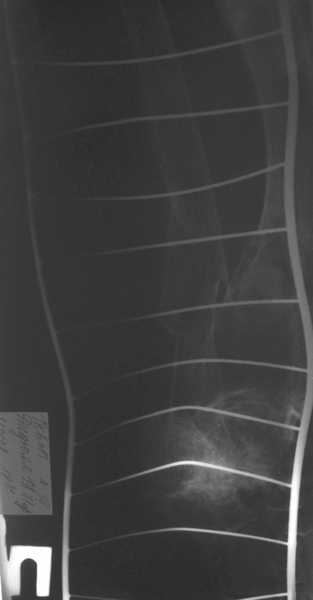

Уважаемые коллеги! Здравствуйте! Прошу у Вас совета вот по какому случаю.В нашу клинику поступила женщина 71 год. Травма в результате ДТП. (Пациентка передвигалась на инвалидной каляске и была сбита автомобилем). Диагноз: Множественная травма. Перелом нижней трети правого бедра. Перелом средней трети правой б/берцовой, малоберцовой кости, нижней трети левой большоберцовой, м/берцовой кости.Травматический шок. Со стороны внутренних органов и систем без патологии. Больная госпитализирована в реанимационное отделение, где было наложено двойное скелетное вытяжение за правую н/конечность. Левая н/конечность иммобилизована гипсовой лонгетой. Из анамнеза: больная является инвалидом 1 группы по опорно-двигательному аппарату. В детстве перенесла рахит. Осложнением которого "О" образная деформация нижних конечностей. Ограничено отведение нижних конечностей, деформирующий артроз тазобедренных и коленных суставов. В 1990 году перелом правого бедра остеосинтез пластиной. После операции больная передвигалась только на костылях или в инвалидной коляске.

Прошу прощения за качество снимков. Р-графия производилась в реанимационном отделении передвижным аппаратом.

Но даже при малоинвазивной методике лечения применимой для даной больной существуют следующие проблемы: выраженный остеопороз, тонкий кортикал, очень широкий канал.

Проблема в том, что в сагитальной плоскости угол голеней =30 градусам. Ширина канала 30.